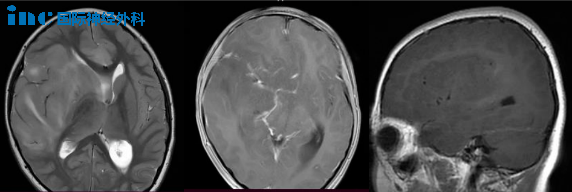

3. 肿瘤恶化快,要先手术吗?

9岁女孩被诊断为脑干病变和梗阻性脑积水。弥漫性脑干病变累及延髓、脑桥和中脑下部,第四脑室受到压迫,导致幕上脑积水。立体定向活检结果显示为儿童弥漫性中线胶质瘤,H3K27改变,WHO4 级。鉴于其30%的高Ki67指数,肿瘤生长速度相当快。

Rutka教授:根据所提供的信息,患儿的肿瘤属于弥漫性内生型脑桥胶质瘤(DIPG),不建议进一步手术切除肿瘤,这也是无法做到的。这个阶段需要进行放射治疗。两种较好选择是传统的三维适形体外放射治疗和质子束治疗。